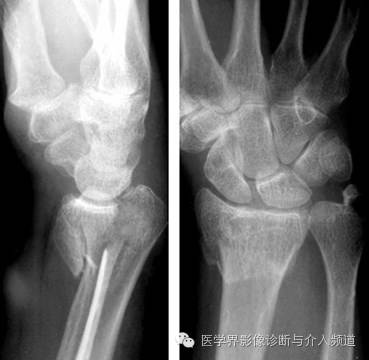

3、Bennett’s骨折

第一掌骨基底部骨折。为关节腔内骨折,非粉碎性,骨折线累及第一掌腕关节面。第1掌骨则由于拇长展肌的牵拉,导致向桡侧和背侧脱位,近端基底部骨块呈四边形。

4、Rolando 骨折

第一掌骨基底部粉碎性骨折并脱位。为关节囊内骨折,需要与Bennett’s骨折鉴别,Bennett’s骨折为非粉碎性骨折,Rolando 骨折有3个以上的骨碎块。